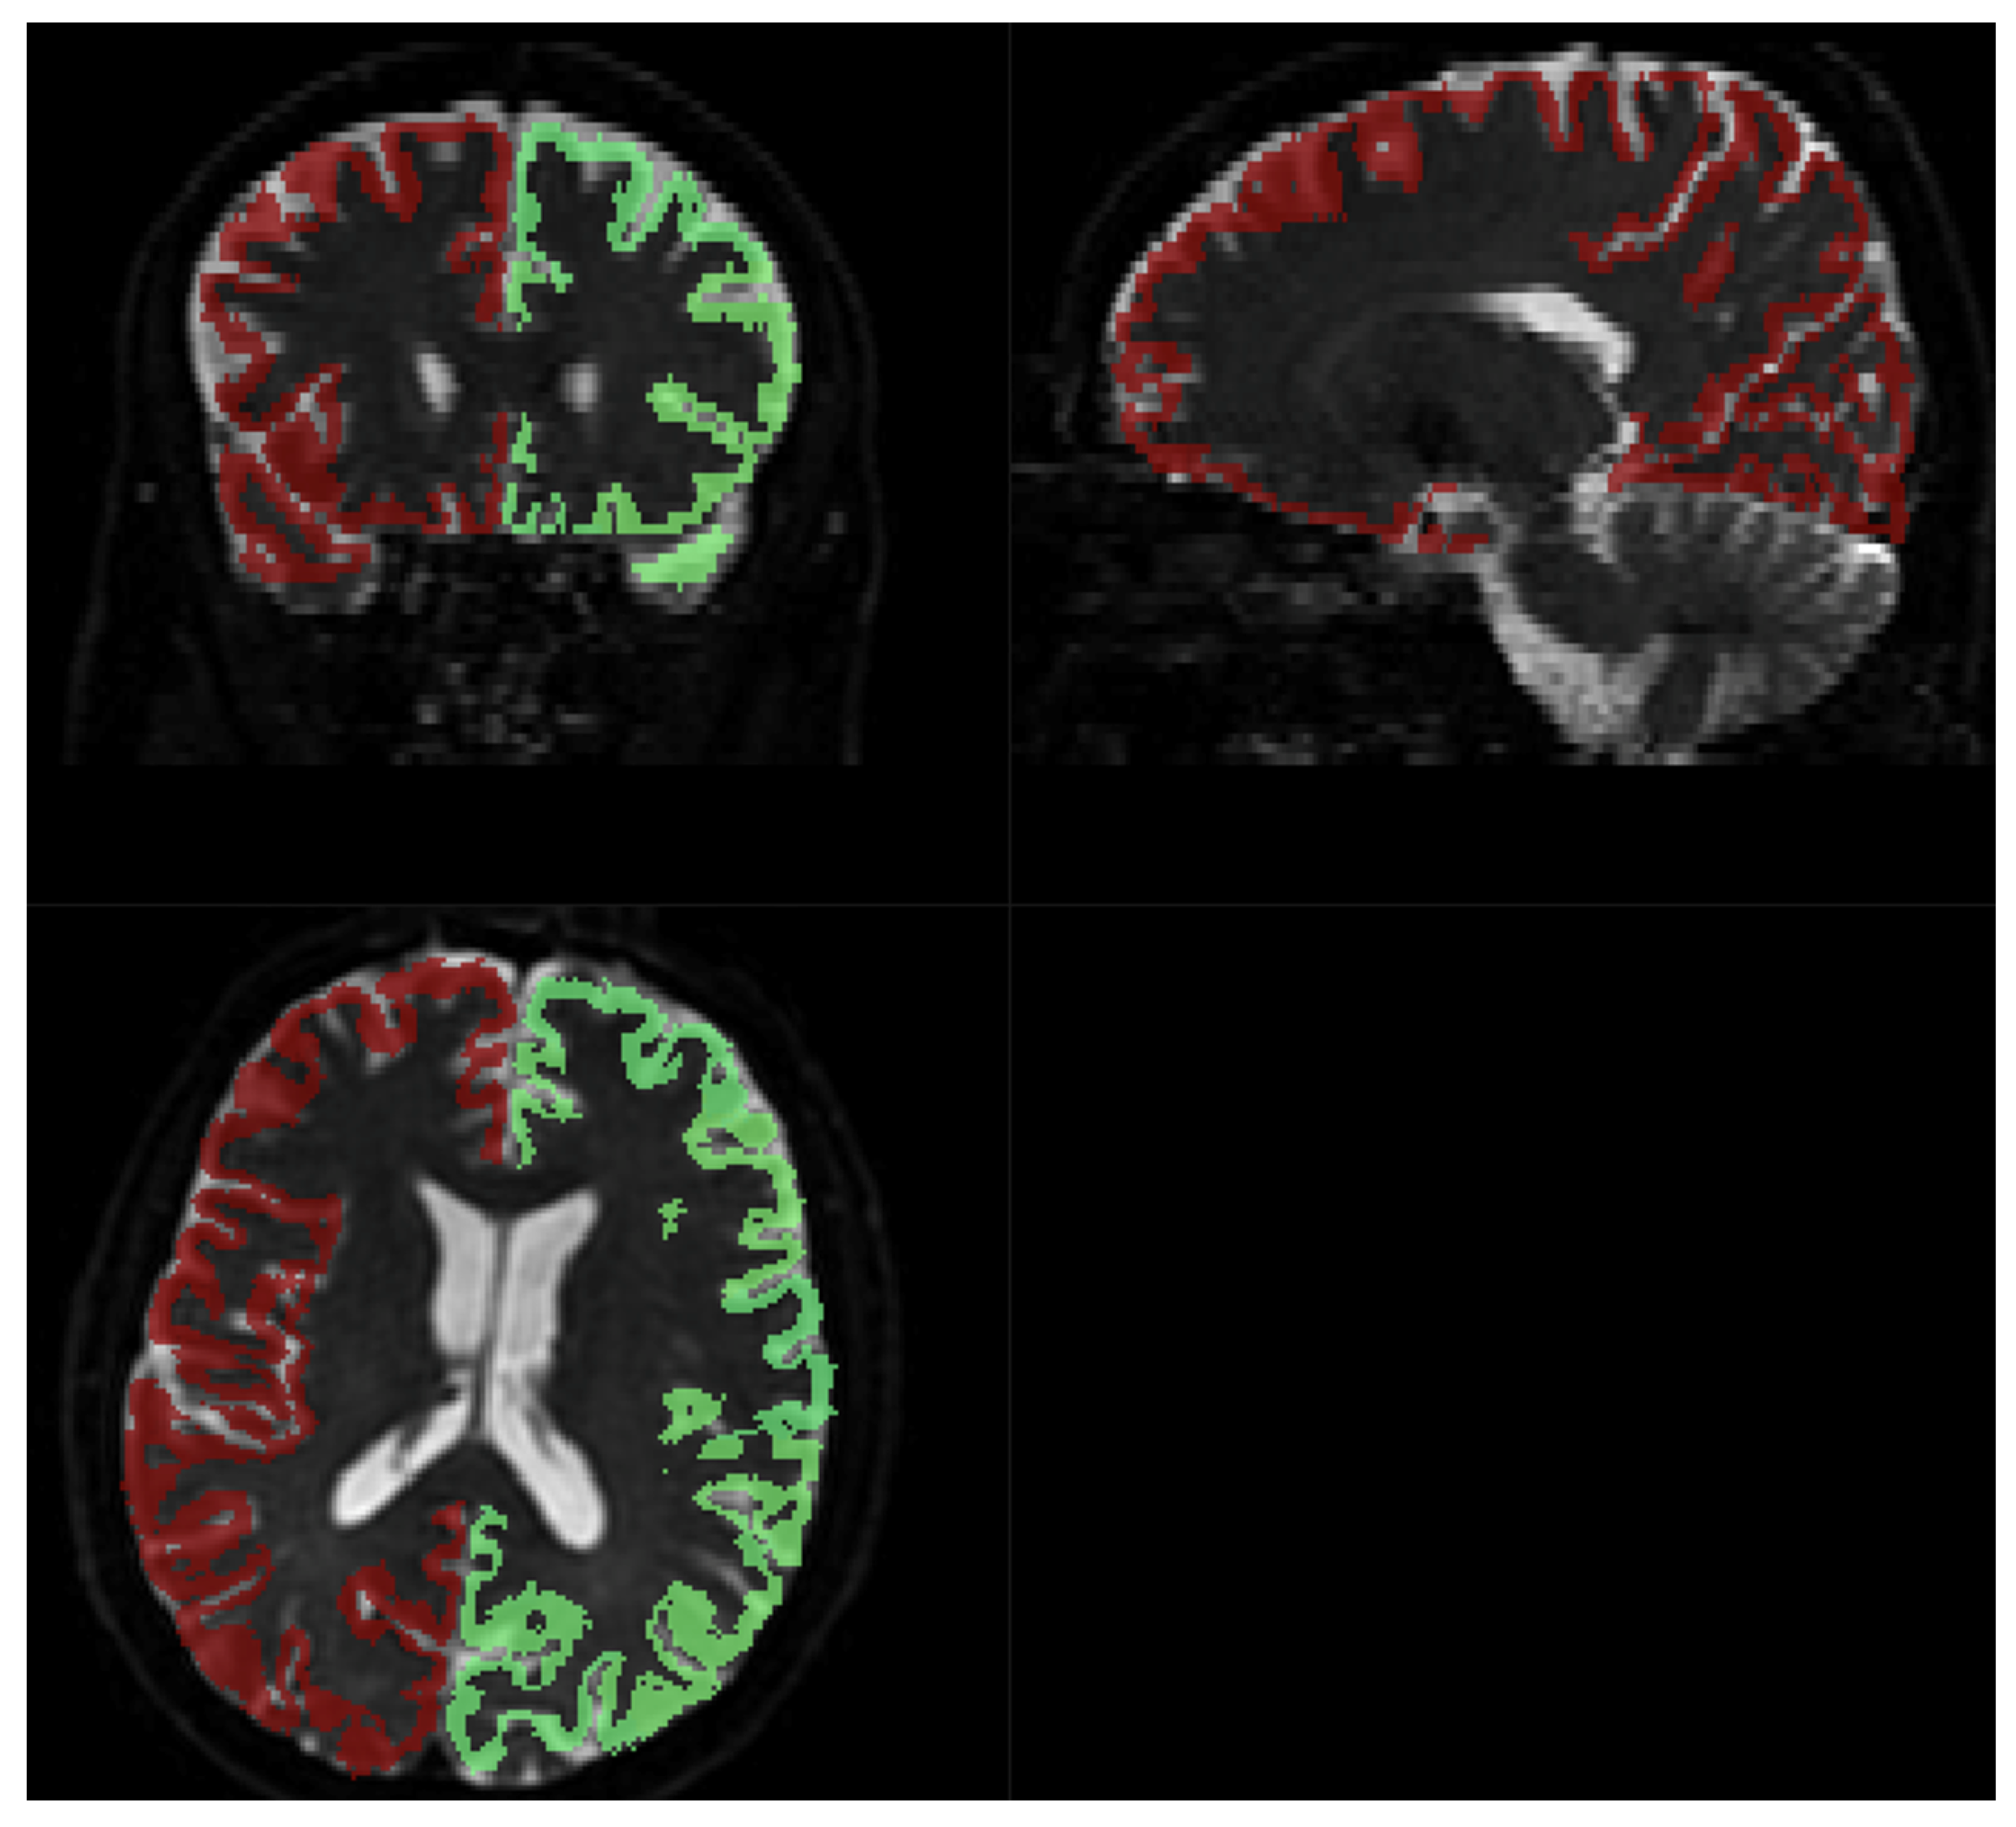

Fitting to the template was performed using MRTRix. The results are depicted in Figure 8.

Figure 8.

Brodmann areas atlas overlayed on DWI scans. Red and green shape represents the coverage of the Brodmann atlas template, regridded to IVIM DWI resolution.

Acquiring high-resolution IVIM DWI allowed for precise spatial alignment with the template/atlas, as evidenced in Figure 8. Visual observation leads to the conclusion that Brodmann’s atlas is mostly well-aligned with cortical structures.